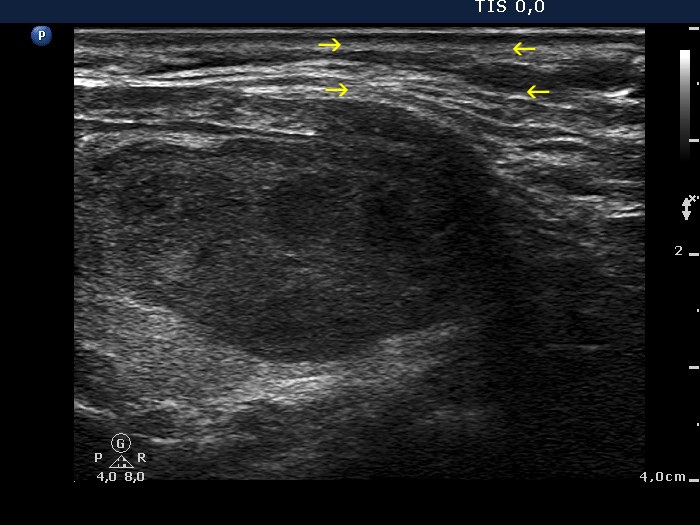

The echogenicity of the nodule - case 33 (ultrasonographic picture 2b)

Right lobe, longitudinal scan. This nodule is moderately hypoechoic (see the video). The deeply hypoechoic parts of the lesion are the consequence of improper fitting of the ultrasound probe to the neck of the patient (yellow arrows).